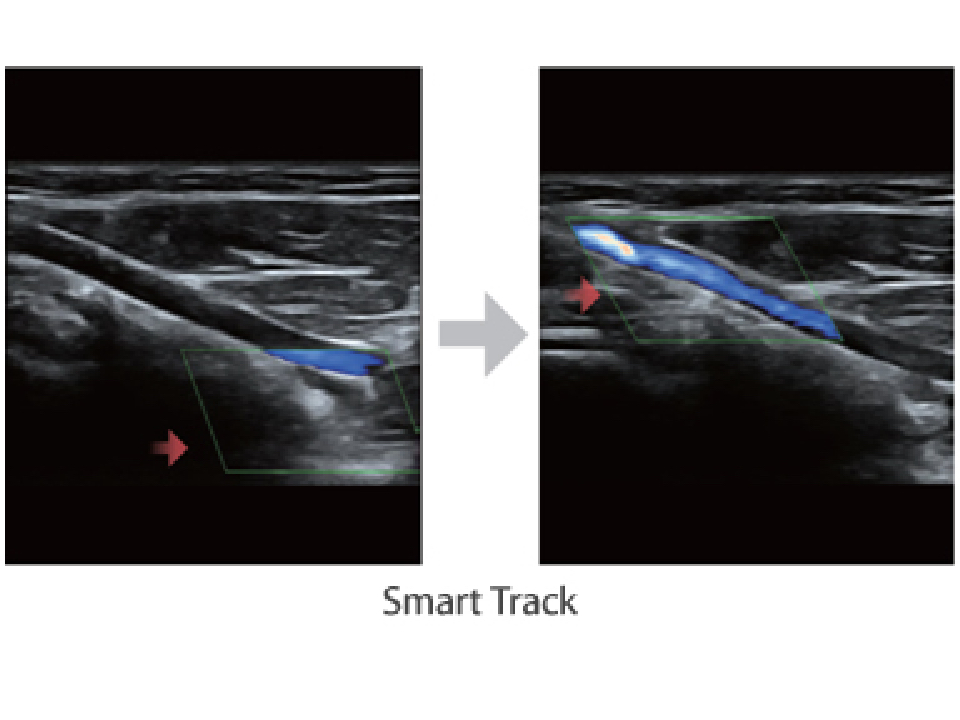

Smart Track

Due to the new platform, the smart track enables to automatically optimize color box and Doppler gate placement accurately, making sure the optimal and best display for color flow and spectral Doppler signal.